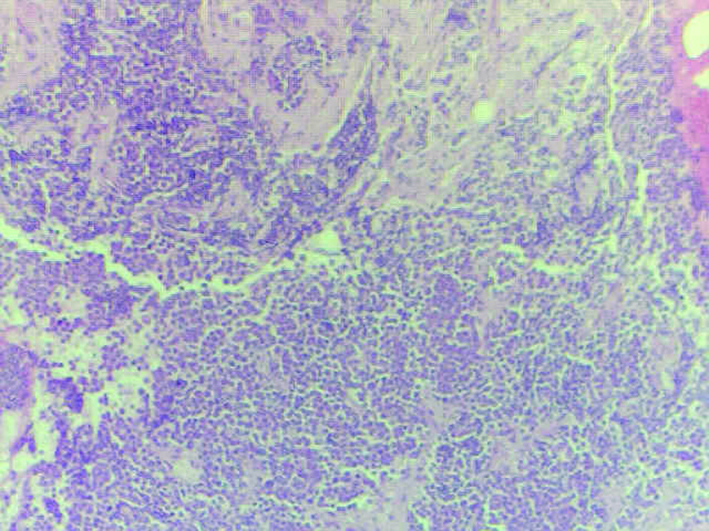

Due to significant anemia and thrombocytopenia, she had a bone marrow biopsy, which showed invasion with small cell carcinoma (Fig. 3).

![]() Click for large image | Figure 3. Bone marrow biopsy. |